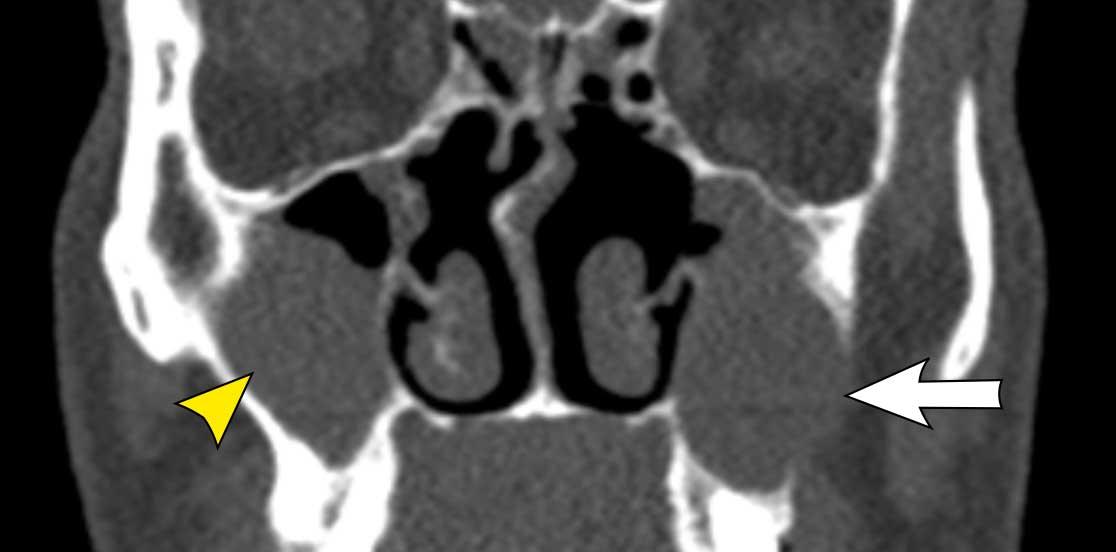

Hình ảnh

Bệnh nhân này có nang nhầy ở xoang hàm trái với giãn rộng nhẹ (mũi tên trắng).

Bên phải có một khối không có giãn rộng (đầu mũi tên vàng) và vẫn còn một ít khí trong xoang hàm.

Đây là nang ứ dịch.

Bệnh nhân này cũng có nang nhầy ở xoang hàm trái.

Bên phải có tình trạng lấp đầy hoàn toàn xoang hàm, nhưng không có giãn rộng.

Do đó, trường hợp này không đáp ứng tiêu chuẩn để chẩn đoán nang nhầy.